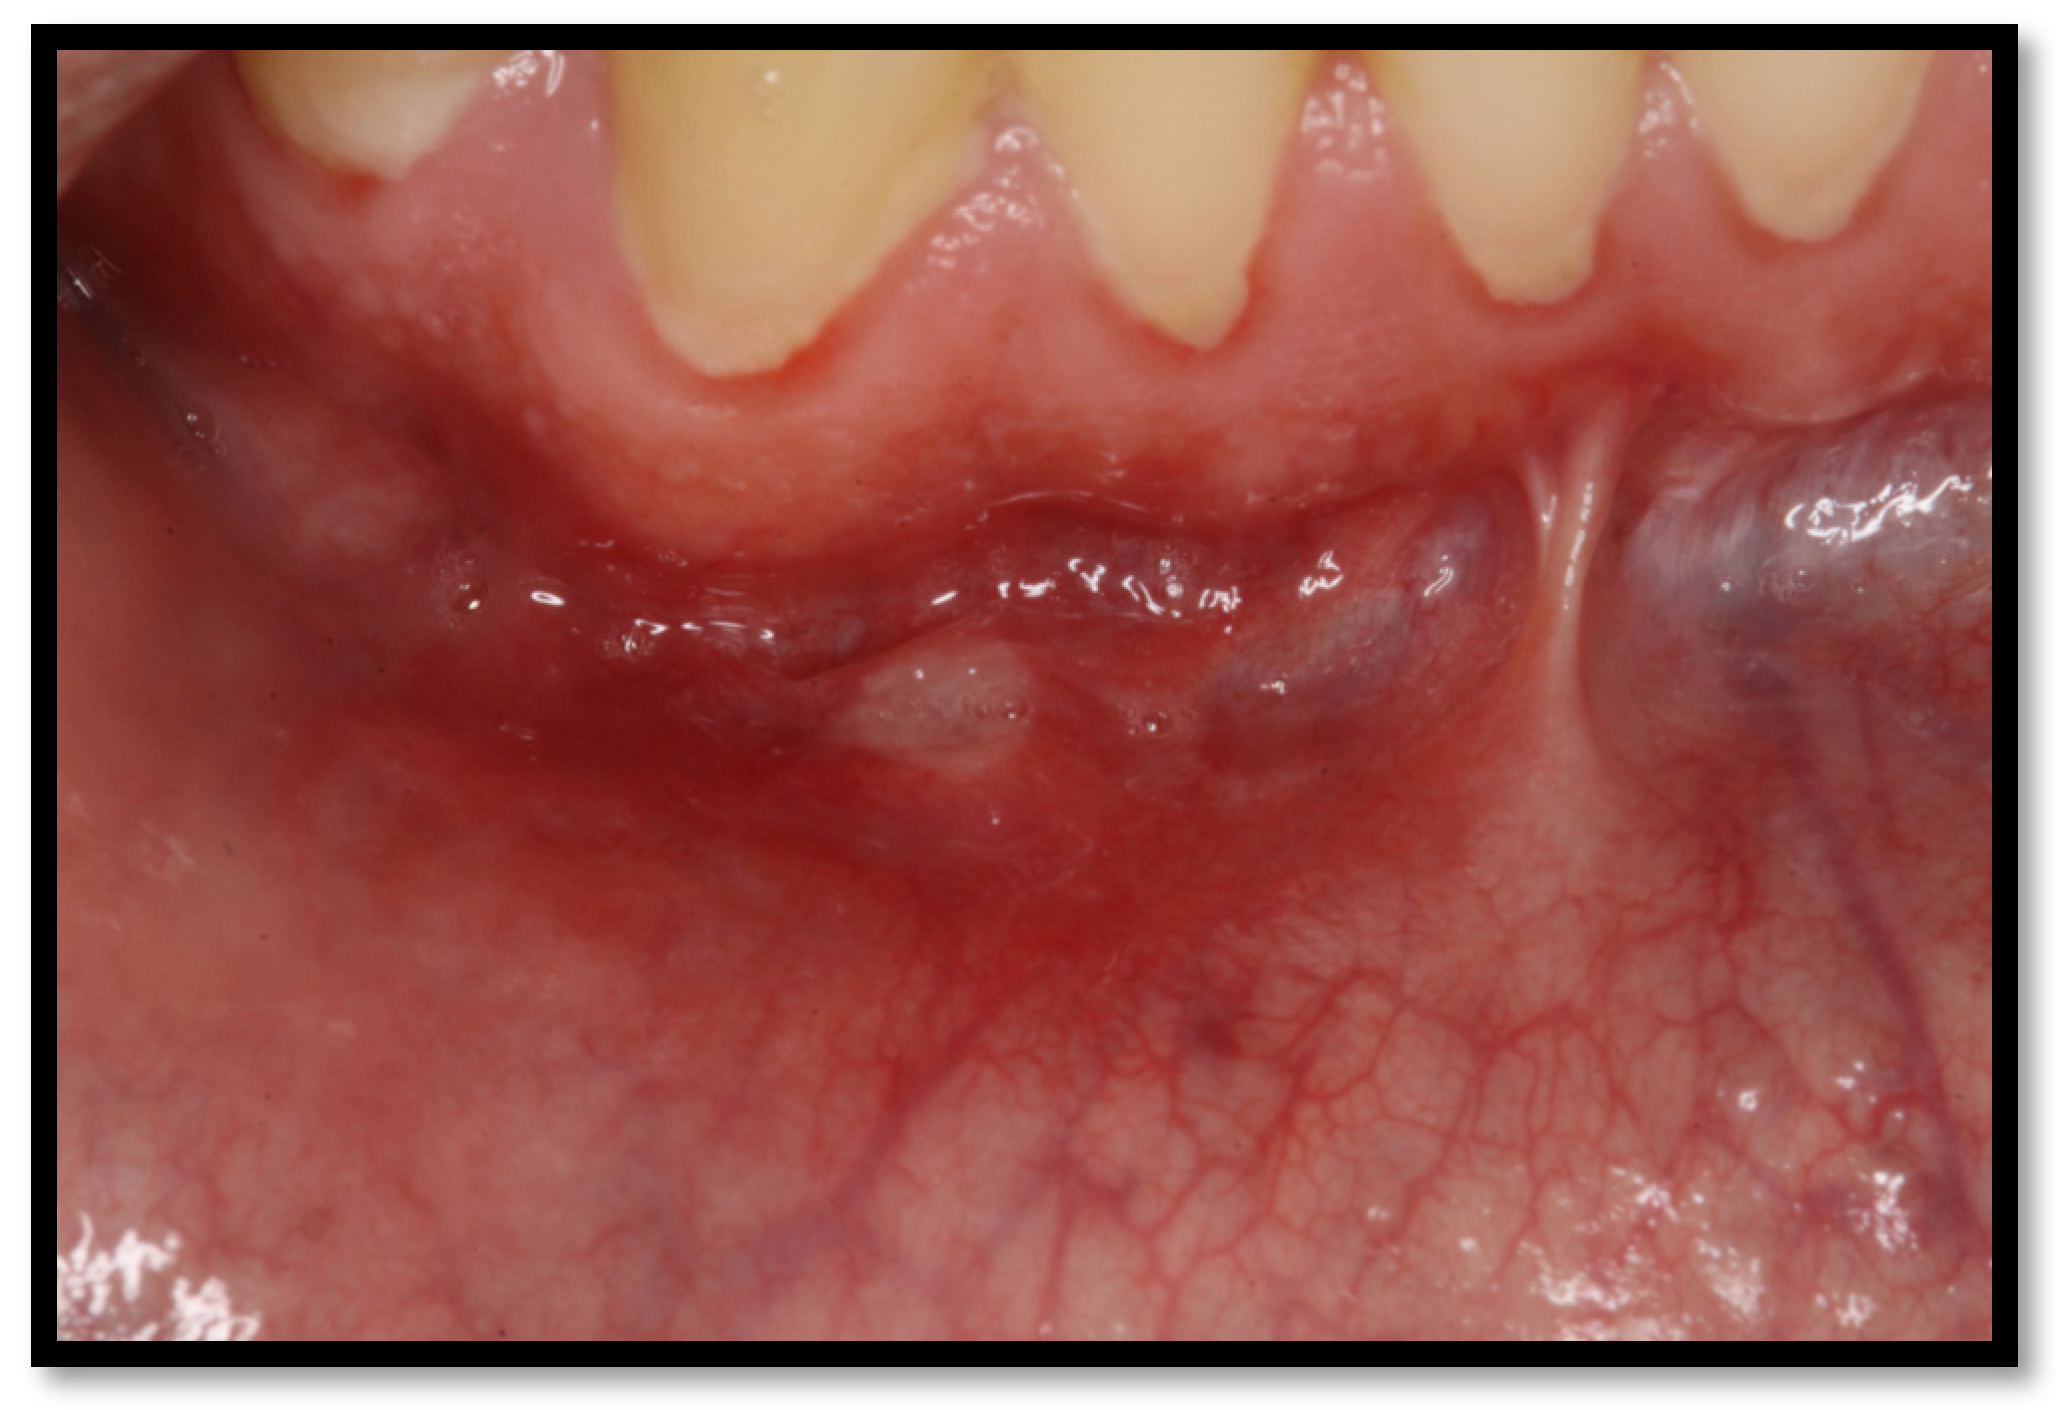

These kinds of ulcers tend to appear most frequently. They usually show up as a simple yet painful erythematous halo, coated with a yellow-grayish pseudomembrane, with a diameter ranging from 2 to 5 mm (Figure 9). Its most common location is on a non-keratinized oral mucous membrane, typically lingering from seven to ten days, healing later without any scarring [4,16,41].

Figure 9.

Minor aphthous ulcer in the lower vestibule mucosa.